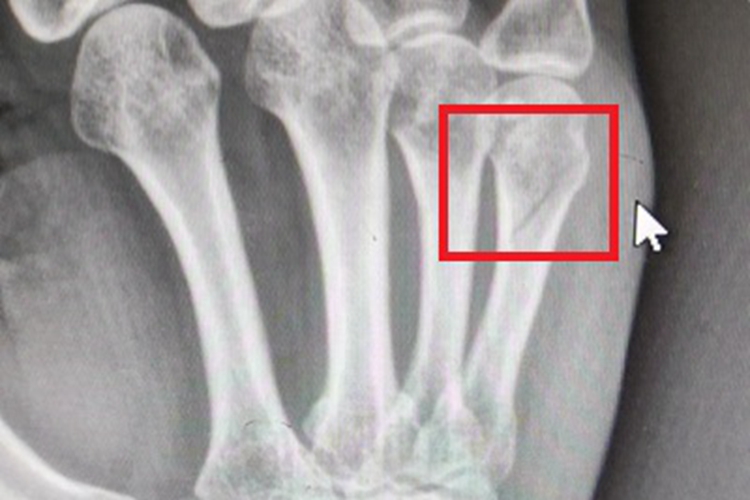

骨折可发生在手掌,患者进行影像学检查时,可见局部有长短、宽窄不一的裂口,断裂面并不规则、平整,患者可能伴有或不伴有骨头错位。自觉有疼痛、肿胀不适,部分患者可因疼痛出现肢体活动受限。

骨折可累及手掌,进行影像学检查时可见局部有断裂面不规则的裂口,长短、宽窄不一。